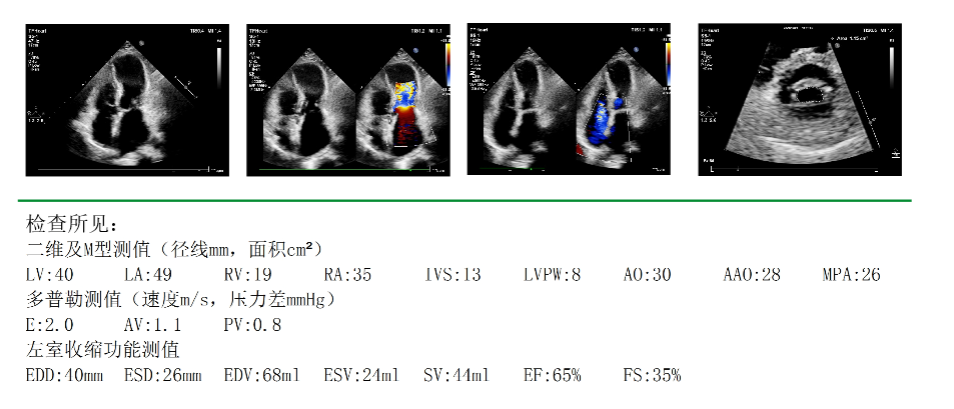

△术前心脏彩超

67岁的江阿姨(化名),最近1年来持续出现活动后心累、心慌等症状,于10月中旬来到华西天府医院心脏大血管外科方智副主任医师处就诊。心脏彩超提示,江阿姨先天性镜面右位心风湿性心脏病,二尖瓣中-重度狭窄,三尖瓣轻-中度反流。